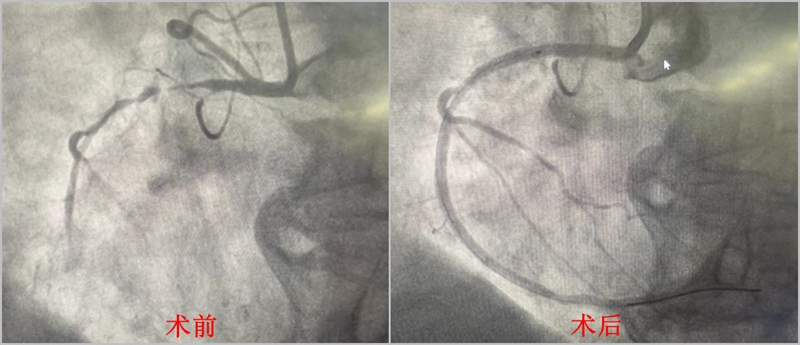

一般心梗手术可通过手部桡动脉血管和腿部的股动脉血管两个路径,谢奶奶年纪大,术后长时间制动困难,容易大出血,从手部桡动脉入径是最佳选择。然而手术开始,医生们却发现谢奶奶的桡动脉、肱动脉扭曲硬化狭窄,救命的通路阻碍重重。

困难时分,救心团队巧施妙计,在支架输送导管上套用“肾动脉导管”,最终顺利开辟通路,成功抵达心脏,入导管室至导丝通过时间仅为30分钟。

术中发现,老人心脏三支血管严重弥漫狭窄病变,右冠近段次全闭塞,病情十分危重。万幸,及时植入支架后,老人化险为夷。术后三度房室传导阻滞也随之消失,心率恢复正常。